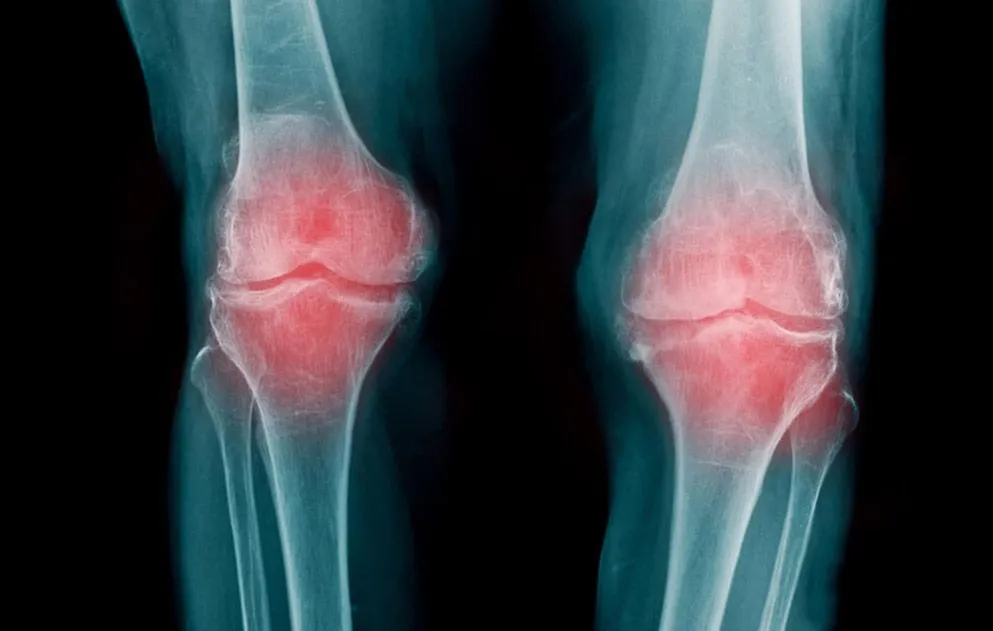

Una de las ventajas para nuestro bienestar que aportan los frutos secos son el alivio a enfermedades degenerativas como la artrosis. En esta afección el cartílago que actúa como amortiguador entre los huesos se desgasta y así estos tejidos comienzan a rozarse entre sí, provocando dolor, inflamación y la limitación del movimiento.

En la artrosis el cartílago que recubre las articulaciones se desgasta.